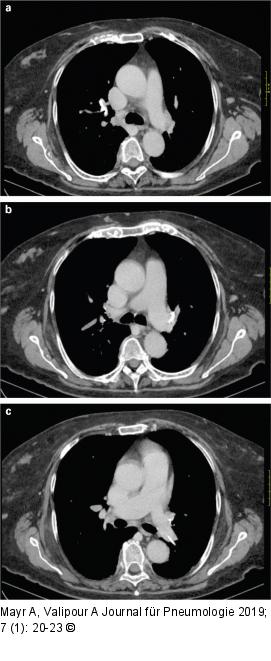

Abbildung 2a-c: Thorax-CT